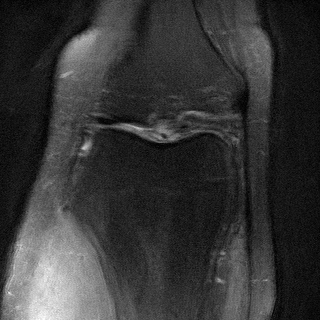

Side

Measurement

ContextMRI

RFJSearch (Ours)

Ground Truth

PDFS with PD

PD with PDFS

| PDFS with PD | ||||

|---|---|---|---|---|

| Algorithm | PSNR () | SSIM () | LPIPS () | NMI () |

| RFJS | 25.85 | 0.801 | 0.375 | 0.457 |

| GS | 25.33 | 0.797 | 0.375 | 0.455 |

| BON | 25.47 | 0.797 | 0.376 | 0.454 |

| ContextMRI | 25.39 | 0.795 | 0.383 | 0.451 |

| PD with PDFS | ||||

| RFJS | 27.85 | 0.920 | 0.358 | 0.579 |

| GS | 27.80 | 0.920 | 0.360 | 0.579 |

| BON | 27.80 | 0.918 | 0.366 | 0.570 |

| ContextMRI | 27.46 | 0.915 | 0.375 | 0.563 |

MRI with multi-contrast side information: Finally, we test on fastMRI knee dataset (Zbontar et al.,, 2018) with the ContextMRI model (Chung et al.,, 2025). We pair PD and PDFS contrasts, reconstructing one from the other under highly accelerated undersampling with 2% ACS. We use normalized mutual information (NMI) as reward, which is robust to contrast changes. Table 6 shows our methods consistently outperform the baseline in all the metrics of interest. Figure 6 highlights sharper edges and more faithful structure.